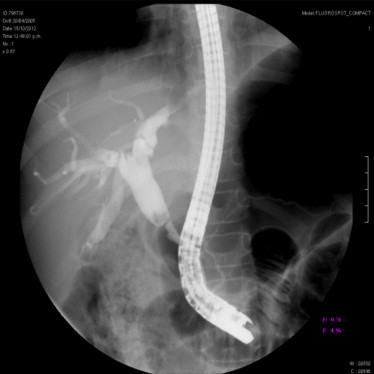

La colangiopancreatografía por resonancia magnética ayuda a demostrar la estenosis, en tanto que la colangiopancreatografía endoscópica retrógrada permite la obtención de piezas para biopsia y estudio citológico para descartar neoplasias malignas.

La colangiografía transhepática percutánea permite la dilatación de la estenosis. La colocación de múltiples endoprótesis de plástico al parecer es más eficaz que colocar una sola de éstas.

La colangiopancreatografía retrógrada endoscópica permite la esfinterotomía para permitir el cierre de alguna fuga de bilis, la dilatación y la colocación de una endoprótesis, para evitar la intervención quirúrgica en algunos casos.